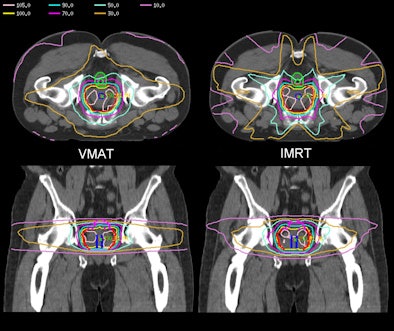

In intensity-modulated radiation therapy (IMRT), a linear particle accelerator sweeps a 1- to 2-cm-wide beam of radiation across the tumor from five to nine angles around the patient, one angle at a time. In contrast, the VMAT method delivers radiation in a single 360° arc while the beam aperture shape continuously changes. Because the resulting beam apertures are much larger in VMAT than in IMRT, treatment time and patient exposure to radiation leakage from the accelerator are reduced.

Zhang and colleagues compared the VMAT technique with standard IMRT using retrospective data from five patients who were prescribed a dose of 86.4 Gy for prostate cancer.

They reported that the VMAT method reduced beam-on time by 50%, down to 2.5 minutes compared with IMRT's typical time of five minutes, with a corresponding reduction in the amount of dose leakage to healthy tissues. Other differences in the treatment plans and outcomes were negligible, Zhang said.

"The main advantage VMAT has over IMRT is that it reduces the monitor unit by 49.8%, and secondary scatter dose to the patient is reduced accordingly," Zhang said.